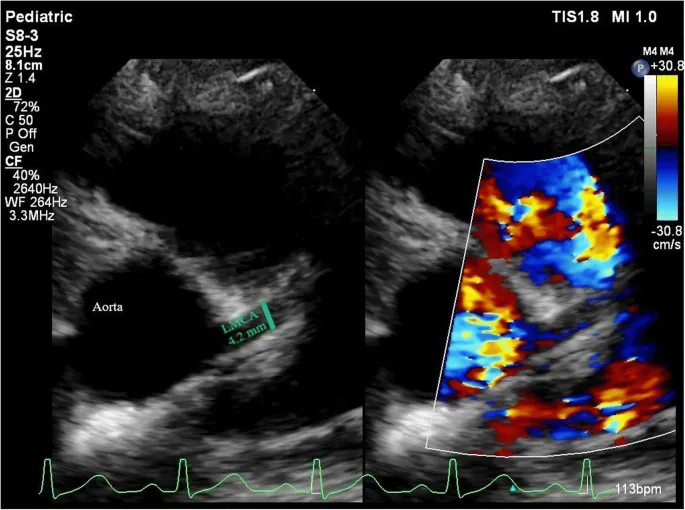

- Diagnosis & monitoring via Echocardiography at baseline, 1-2 weeks, and 4-6 weeks after treatment.

- Classified by z-scores (internal diameter):

- Small: z ≥2.5 to <5

- Medium: z ≥5 to <10

- Giant: z ≥10 or >8 mm diameter.

- Echocardiography is the gold standard for diagnosis and serial monitoring of coronary arteries.